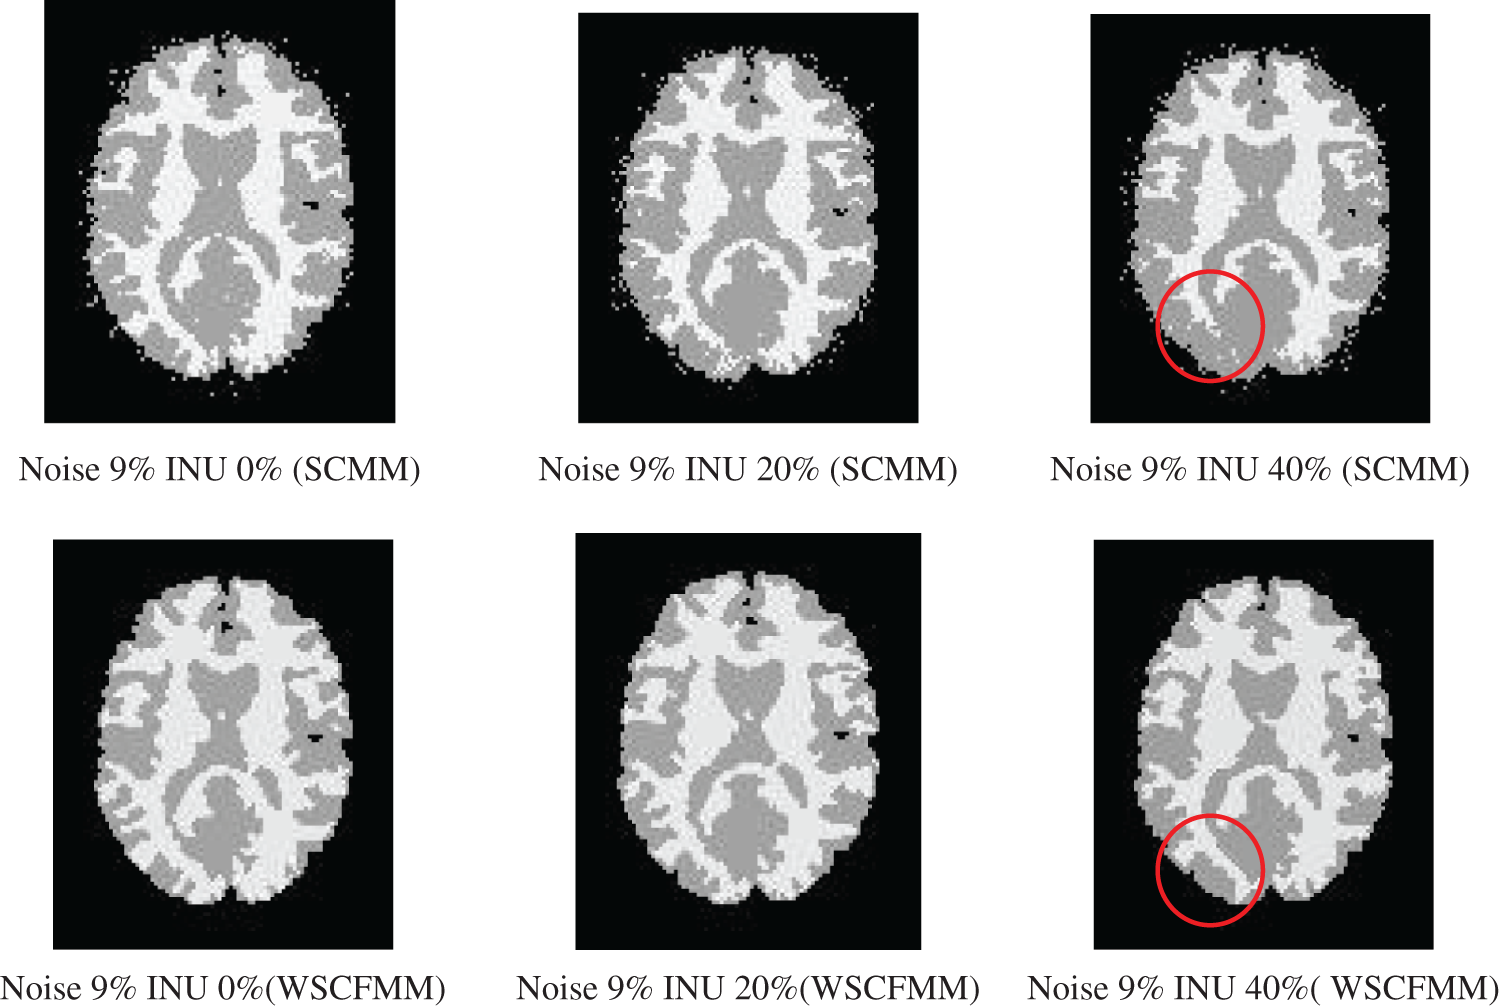

The visual comparison between the results produced by both the models showed that WSCFMM was able to control the outliers and gave an appreciative level of performance in ideal conditions and in conditions where the candidate image is affected from intensity INU and/or noise.

Figs. 3 and 4 show the performance of WSCMM in comparison to SCMM. The results shown in the figures were obtained from the images affected with a higher level of noise, i.e., 7% and 9%, combined with different levels of INU. The visual investigations of these results show that besides outliers, SCMM is also unable to provide a well-defined segment. The circled region in Figs. 3 and 4 provides important observations which led us to the conclusion that a substantial portion of the information is missing. However, at the same settings of noise and INU, WSCFMM not only controlled the outliers but it also captured that missing information.

Figure 4: Visual comparison of images with 9% noise and INU varying from 0% to 40% segmented by SCMM and WSCFMM